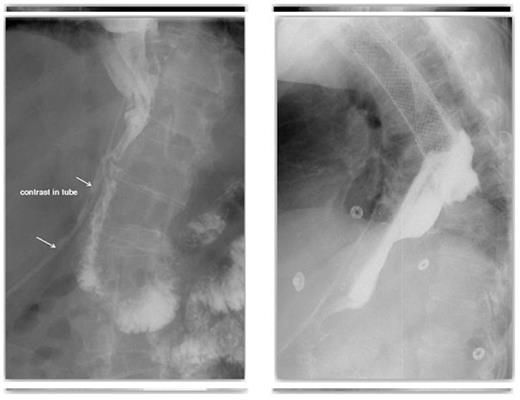

Follow up CT, with contrast both orally and through the T-tube, showed no evidence of ongoing leak from the pyloroplasty. The flanged T–tube satisfactorily plugged the hole through the anterior wall of the pyloroplasty, best demonstrated in the lateral decubitus position (Figures 7 and 8).

The T-tube was then capped off and the pigtail drain subsequently removed. The patient was commenced on oral fluids and progressed to oral diet. The patient was discharged with a capped off T-tube in situ and made a good recovery.

A follow-up CT demonstrating no evidence of on-going leak from the pyloroplasty & A follow-up CT demonstrating the flanged T-tube satisfactorily plugging the hole through the anterior wall of the pyloroplasty